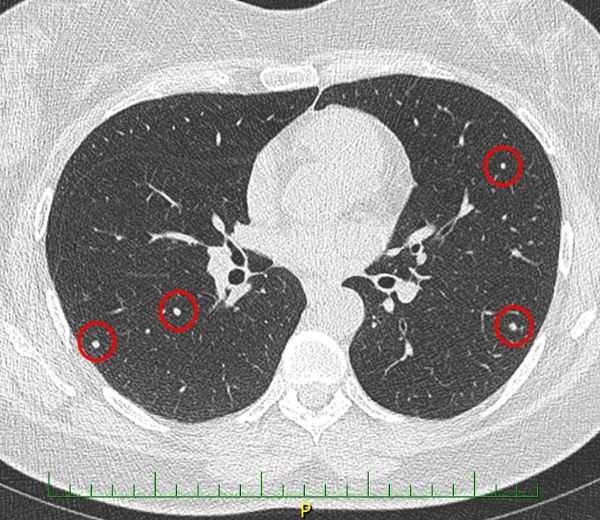

CT

A 37-year-old woman, Lucie Pospíšilová, attends her general practitioner complaining of persistent pain in her left armpit.

author: MUDr. Zuzana Čermáková, publicated: 12.03.2019